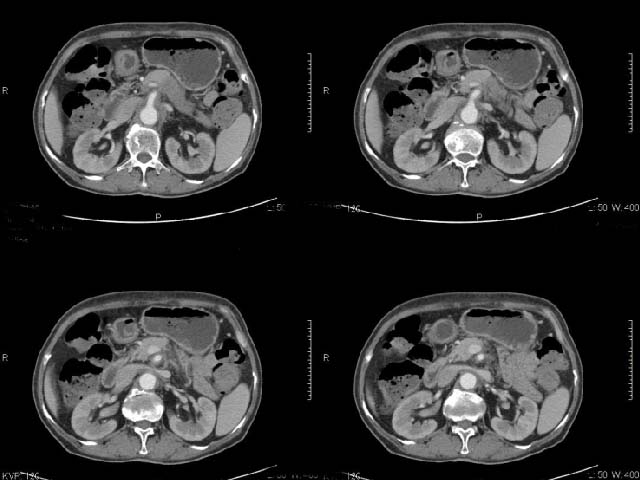

女,69岁,浑身乏力,腹泻半年余,无腹疼,排泄物中含有脂肪球,抗炎治疗一周仍不缓解,来我院检查发现明显低钾血症,给予补钾(氯化钾)一周后,血钾恢复正常,经化验检查,尿钾持续明显高于正常,临床考虑患者不仅消化道失钾,还伴有泌尿系统失钾,故进行ct增强检查看肾上腺是否有病变。ct表现为胰腺肥大,而且体尾部强化较弱,明显呈稍低密度,胰尾见有更低密度,而且胰腺与周围组织的脂肪间隙不清,大血管周围似乎有包绕现象,患者是否有过胰腺炎病史,家属说不清楚;而双侧肾上腺大小形态,本人认为未见异常,本人倾向于考虑:慢性胰腺炎伴假性囊肿,不排除胰腺占位可能;但是不知怎么解释持续尿钾现象。请大家发表高见!

平扫